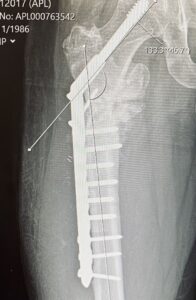

- Work got feverish then we all went to Amsterdam. I gave a ‘burst’ (4 minute talk) on 1-3-10-30 and hung around a stand with it on to talk to people about it. At some point in the next 24 hours my leg re-broke (but I thought I’d just pulled muscles)

- Spent most of the month in pain and working from home. At the end of the month went for an x-ray where they confirmed the leg was broke again.

- Had a bunch of scans, tests and negotiated with an anaesthetist so that I could have surgery at the end of the month. Did that surgery.

- VV’s birthday. Lots of Peppa pig. Me attempting to be in convalescence but back to where we were at the start of this post. Scans look good apparently but the consultant says ‘hope’ a lot.